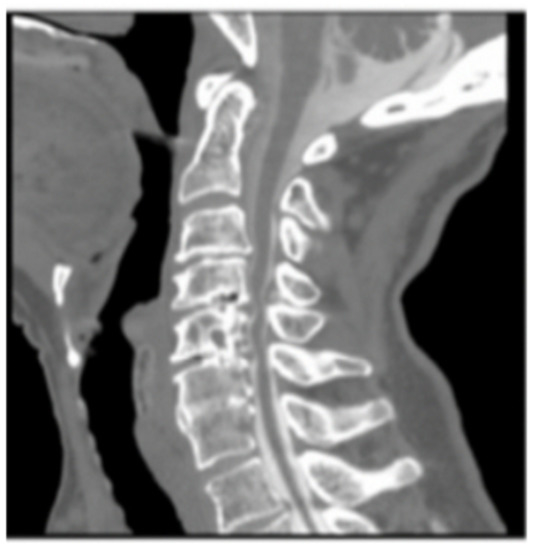

The patient was asymptomatic immediately post-op. Computed tomography (CT) angiography showed anterolateral bony defect at C5 (Figure 2). The study also revealed 50% focal narrowing of the left VA at C5; consistent with focal thrombus versus external compression possibly due to bone wax (Figure 3). The study confirmed acceptable cervical alignment, operative decompression, and hardware placement.

Figure 2. Computed tomography (CT) Scan (arrow denoting bony defect C5).